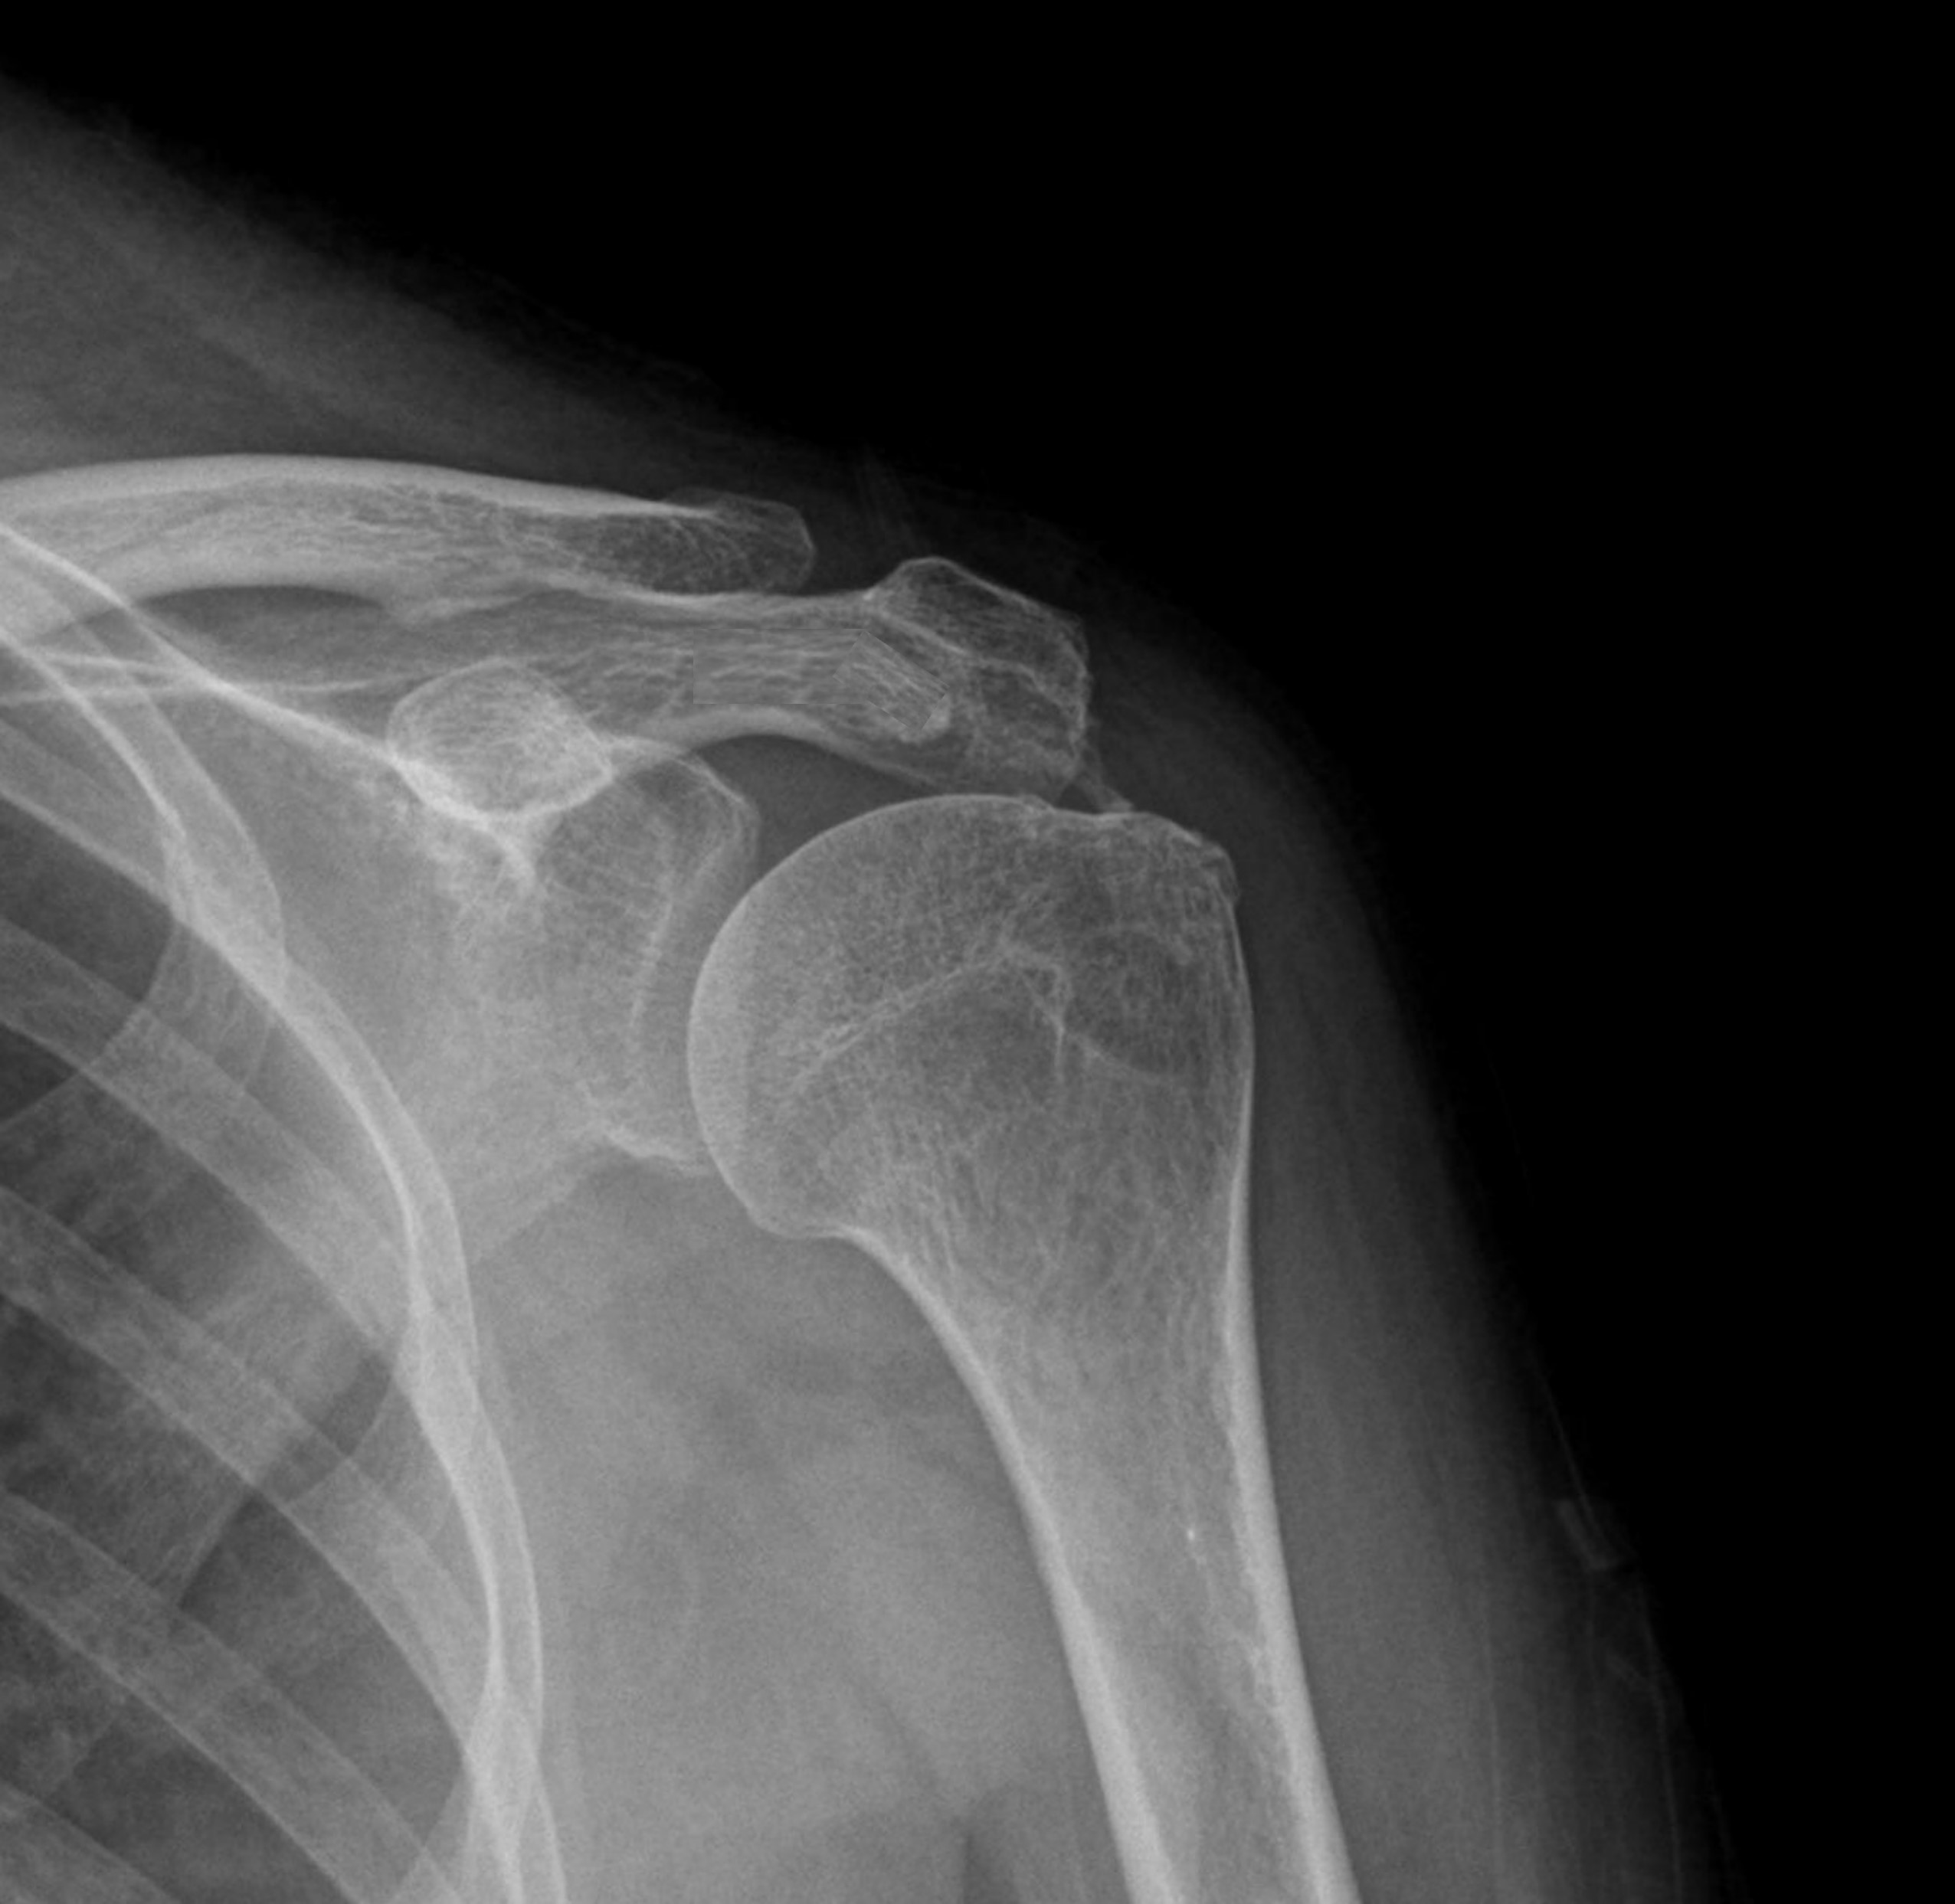

케이스 1: 형성기 단단한 석회 (1회 제거)

환자: 50대 남성, 우측 어깨 통증 8개월

시술 전:

X-ray에서 약 1.5cm 크기의 석회 확인

형성기 석회 (매우 단단)

타 병원에서 "수술 권유" 받음

시술 후:

1회 분쇄흡입술로 완전 제거

시술 직후 X-ray에서 석회 없음 확인